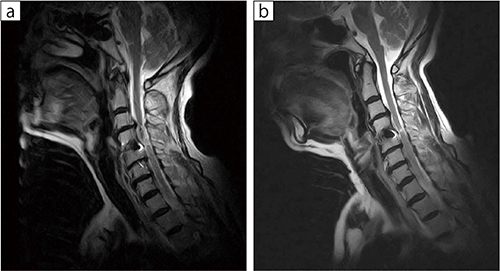

■症例1:頸椎症術後

70歳代,女性。APERTO Lucent Plus(b)では,Lサイズ関節コイルを用いることで体動の影響が軽減され,脊髄の細部も良好に描出できた。

a:APERTO Lucent b:APERTO Lucent Plus

T2WI,TR/TE:2500/120,スライス厚:4.5mm,FOV:250mm,FA:90°,撮像時間:3:33